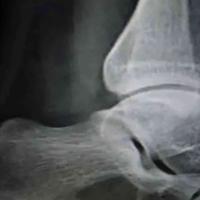

滑膜软骨瘤?

查看图片需登陆

滑膜软骨瘤?...

由 medjpg 发表于 2026-03-24 22:32